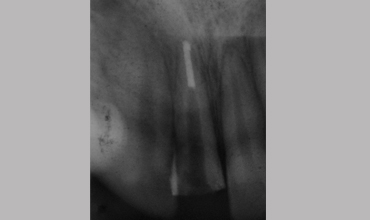

Management Of Radix Entomolaris In Mandibular First Molar